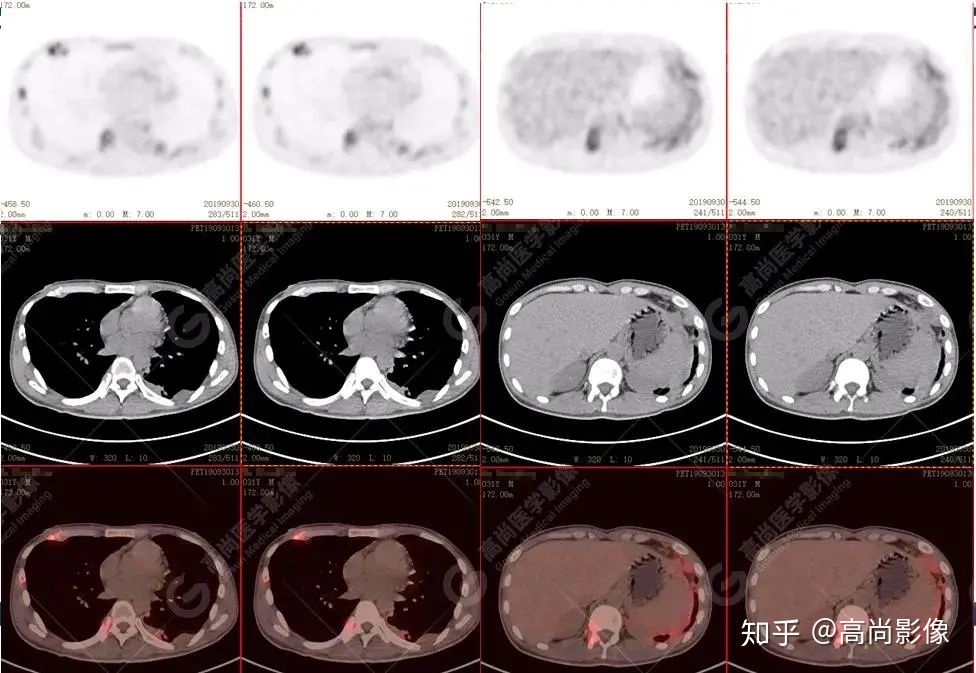

左肺上葉尖后段及下葉背段多發(fā)簇狀斑點(diǎn)狀高代謝灶

左側(cè)胸膜結(jié)節(jié)樣增厚,代謝不同程度增高